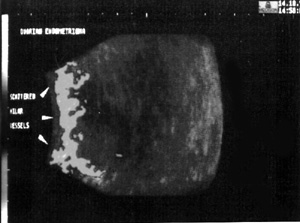

Η χρήση των 3D power Doppler στο μέλλον μπορεί να επιτρέψει την καλύτερη απεικόνιση του τοιχώματος, του εσωτερικού περιεχομένου και της αγγείωσης των ενδομητριωσικών κύστεων και να συμβάλει με μεγαλύτερη σαφήνεια και ακρίβεια στη διαφοροδιάγνωσή τους από τις άλλες καλοήθεις και κακοήθεις κύστεις των ωοθηκών. Στην 3D power Doppler υπερηχογραφία τα αγγεία των σοκολατοειδών κύστεων είναι συνήθως ευθέα, ομαλά διακλαδιζόμενα που ξεκινούν από ένα αγγείο της πύλης και διατρέχουν κατά μήκος της επιφάνειας του τοιχώματός τους (εικόνα 1).(9)

Εικόνα 1. Χαρακτηριστική αγγείωση ενδομητριώματος στην 3D power υπερηχογραφία.